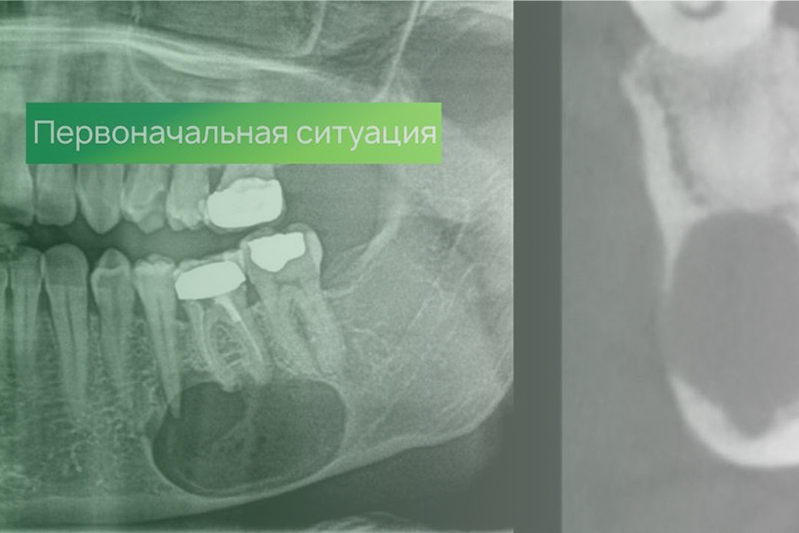

Клинический случай. Хирургия

22 апреля 2020